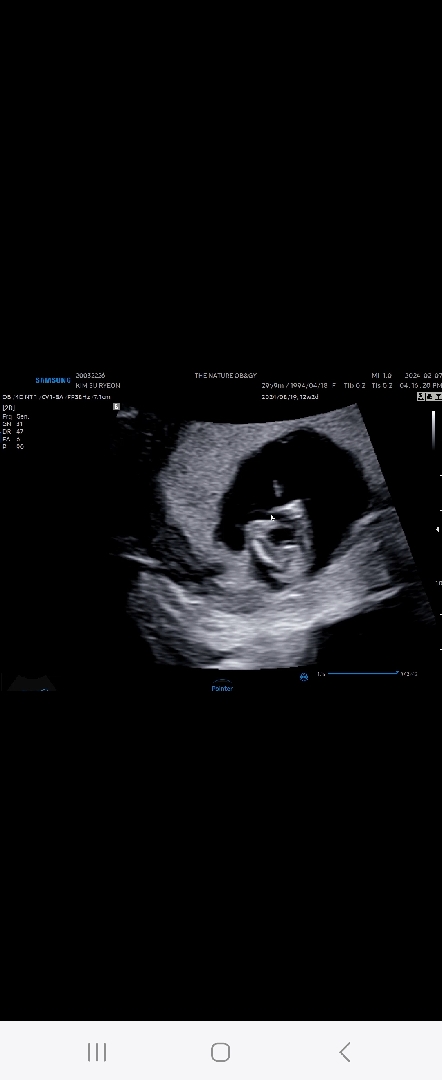

각도법 주로 보는 방향인 초음파사진은 성기가 가려져서 아예 판별할 수가 없고요 ㅠㅠ 이건 밑에서 본 다리 두개랑 엉덩이쪽이에요!ㅎㅎ 이걸로도 아들 딸을 예측할 수 있을까요?? 참고로 12주 6일입니당 ㅎㅎ